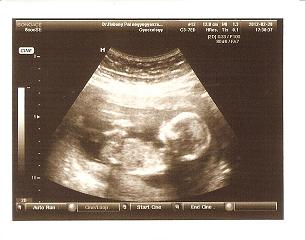

Gratula az újabb fütyishez.